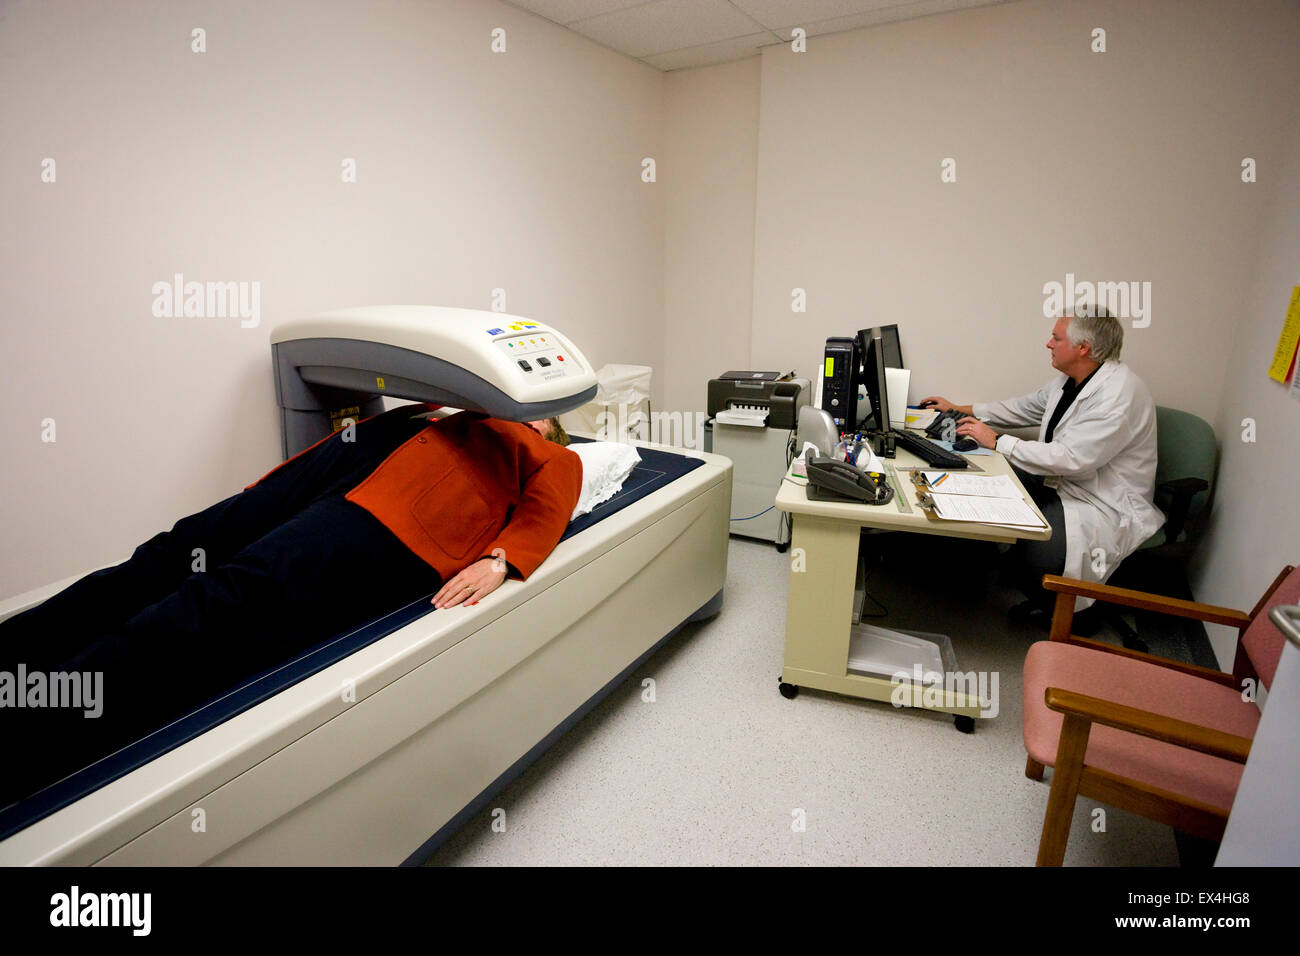

patient receives bone density scan used to measure calcium content of bone and bone loss Stock Photohttps://www.alamy.com/image-license-details/?v=1https://www.alamy.com/stock-photo-patient-receives-bone-density-scan-used-to-measure-calcium-content-84924120.html

patient receives bone density scan used to measure calcium content of bone and bone loss Stock Photohttps://www.alamy.com/image-license-details/?v=1https://www.alamy.com/stock-photo-patient-receives-bone-density-scan-used-to-measure-calcium-content-84924120.htmlRMEX4HG8–patient receives bone density scan used to measure calcium content of bone and bone loss